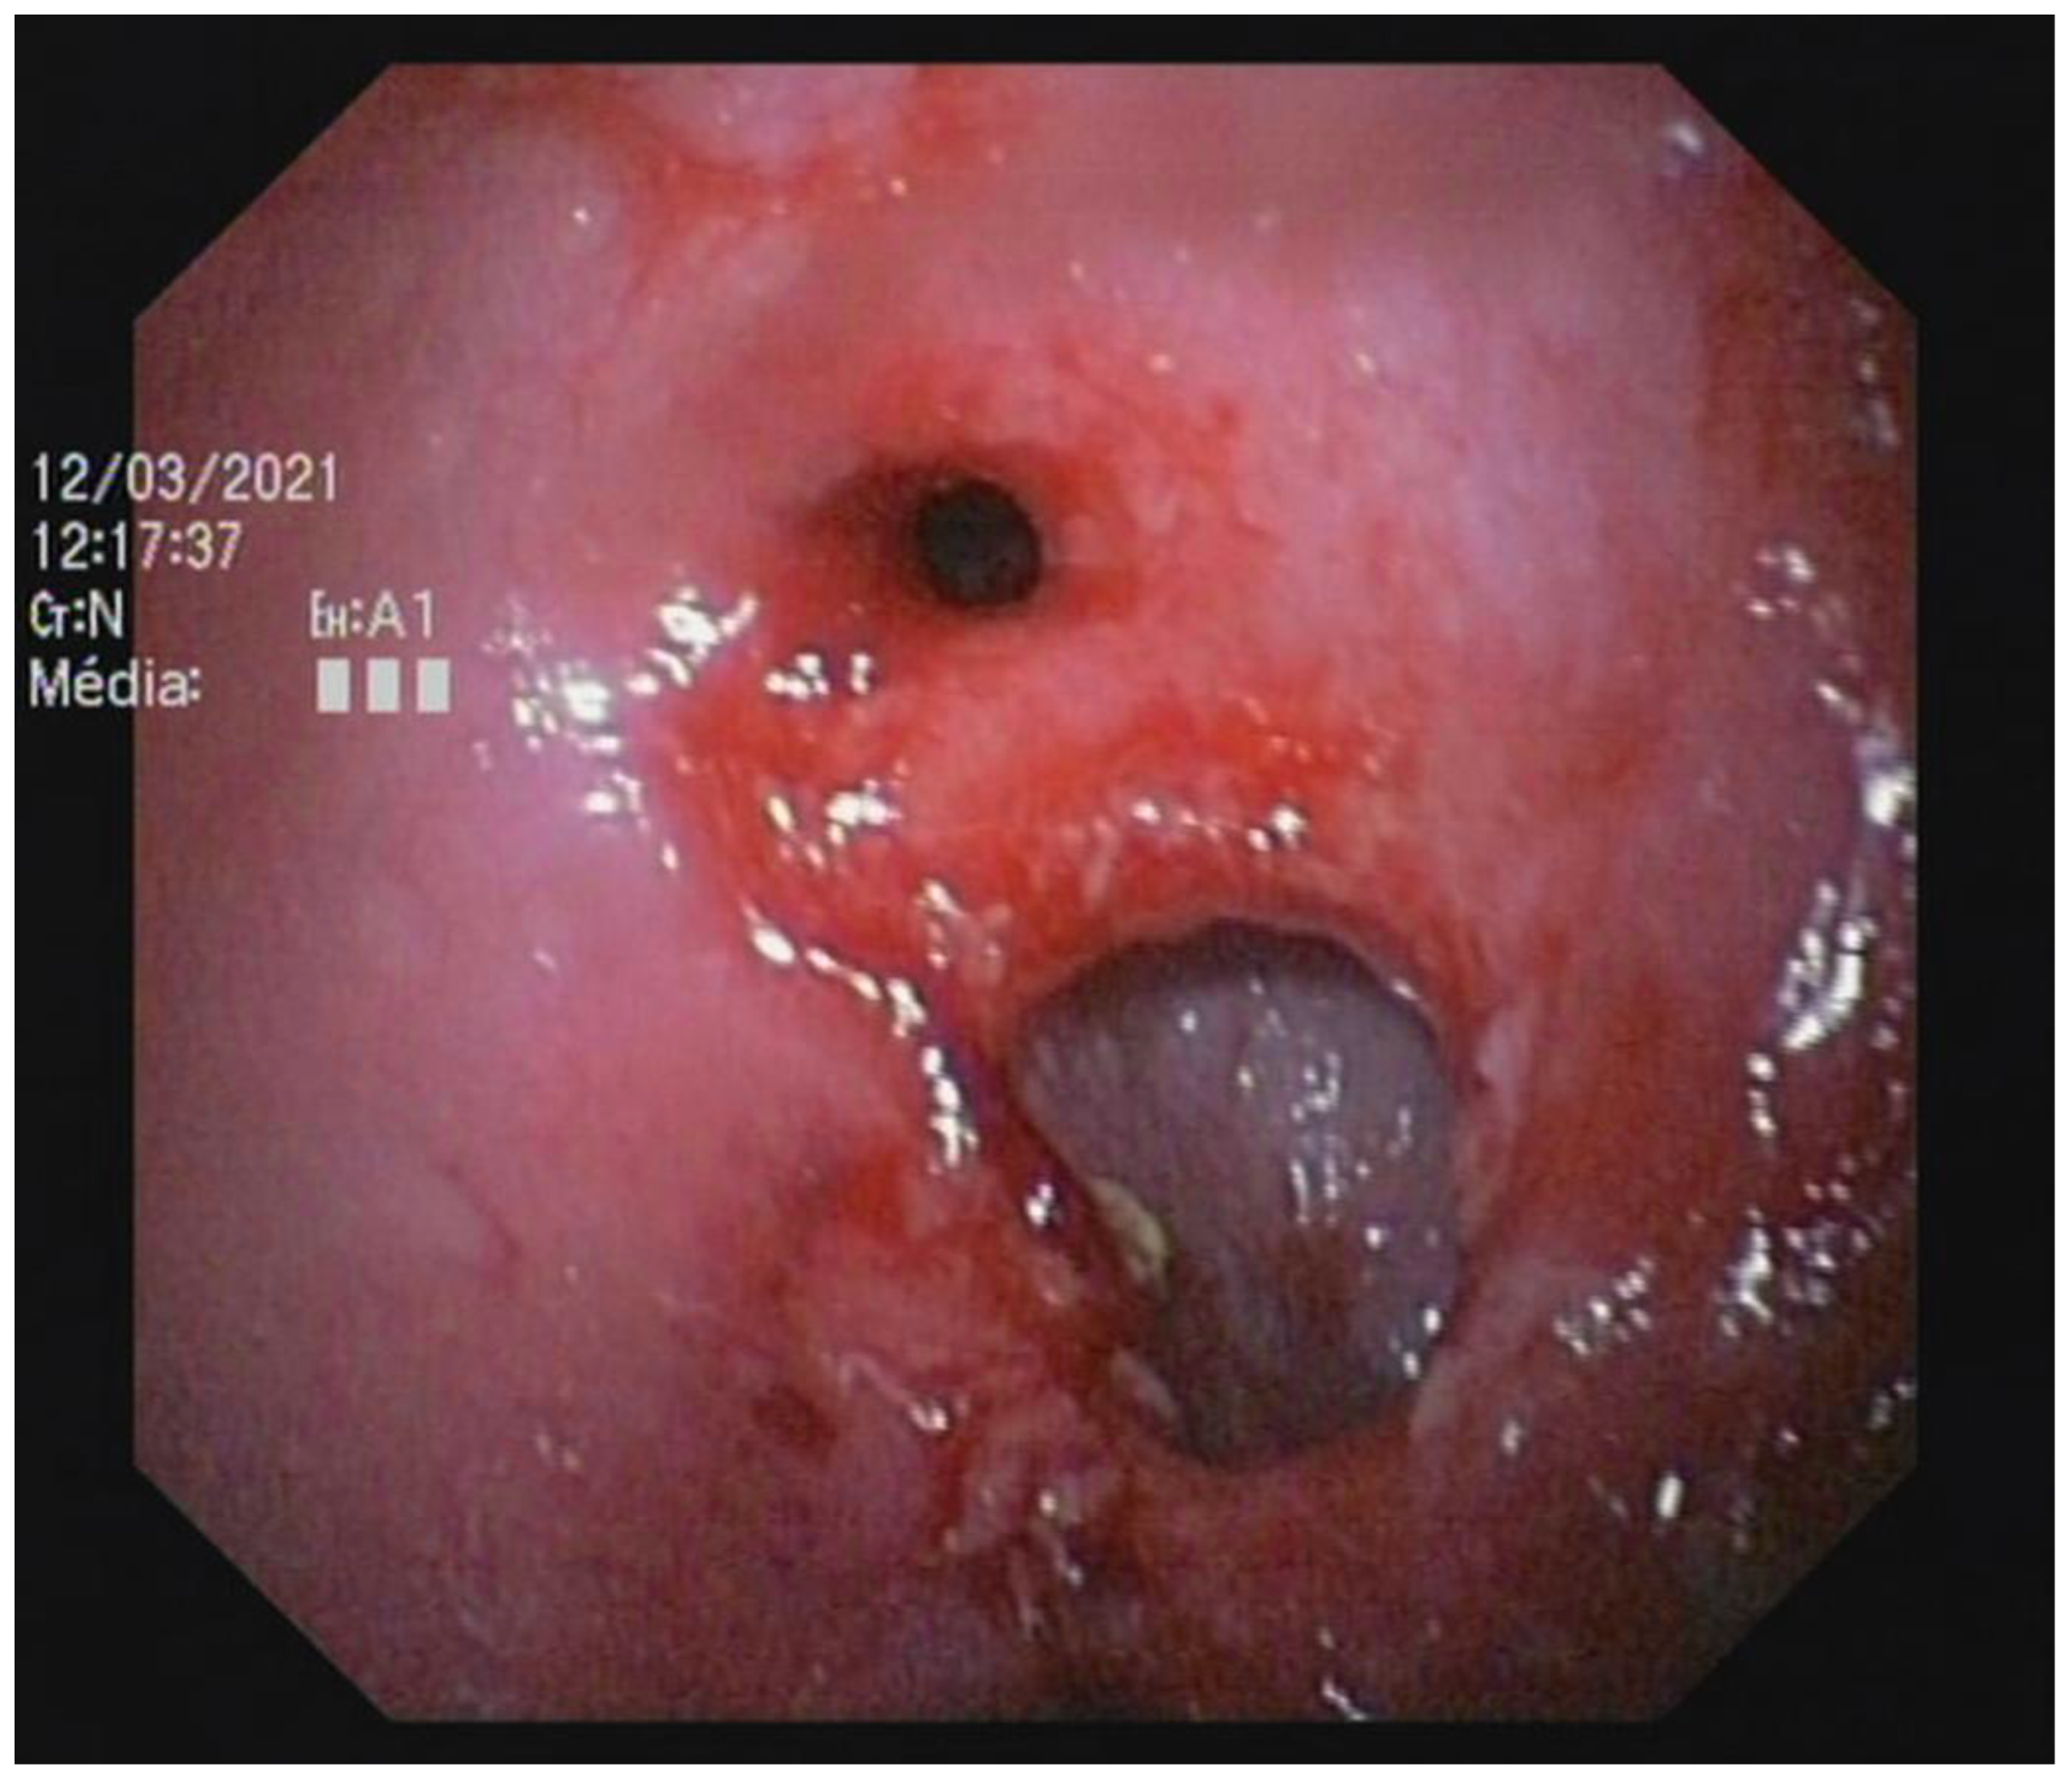

Endoscopic abnormalities are presented in Table 6 and included: gaping, atone and opened ileocolic junction in 8 cases (4 in group A and 4 in group B, Figure 5), absence of cecum in one case, colonic stenosis of variable degree in 12 cases (2 in group B and 10 in group A, Figure 6), erosive or marked macroscopic signs of colopathy in 5 cases (5 in group B and 3 in group A), non-specific slight to moderate signs of colopathy in 8 cases (3 in group B and 5 in group A) and unremarkable colon in two cases (one in group A and B).

Colonoscopy allowed the diagnosis in most cases. Partial colonic agenesis was associated with other anatomical malformation in 8 cases and included absence of the cecum or abnormal ileocolic junction (Image 3). Focal stenosis was also identified in 12 cases. Marked macroscopic signs of active colonic disease were identified in 5 cases and corresponded to a diagnosis of granulomatous inflammation or IBD. In most cases however, the colic mucosa was macroscopically normal or only slightly modified, especially in group A.

Figure 6. Focal colonic stenosis in a cat (Case 15).